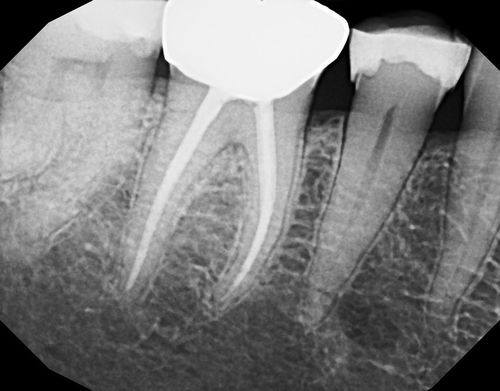

Staying at the forefront of dental technology provides our patients with the best possible results. Within our state-of-the-art practices, you'll find microscopes, digital radiography, and 3D imaging, all seamlessly integrated into our daily practice. This enables us to deliver a higher caliber of care so treatments go easier – offering more comfort and excellent results.